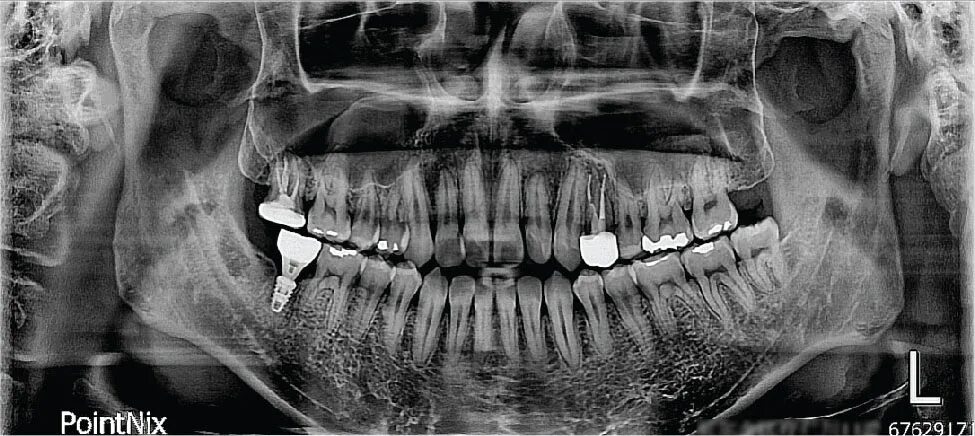

Снимок ротовой полости